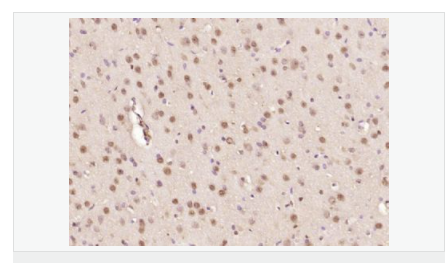

細(xì)胞定位細(xì)胞核 細(xì)胞漿

產(chǎn)品介紹The human ataxin-7 gene, also known as spinocerebellar ataxia 7 or SCA7, maps to chromosome 3p13-p12, has a 2,727-bp open reading frame, and encodes a 892 amino acid protein containing a nuclear localization signal and a polyglutamine tract (1,2). SCA7 is an autosomal dominant neurodegenerative disorder characterized by ataxia and selective neuronal cell loss caused by the expansion of a translated CAG repeat encoding a polyglutamine tract in ataxin-7, which is the SCA7 gene product (3,4). Ataxin-7 is expressed within neurons both affected and unaffected in SCA7 pathology with subcellular localization being variable depending upon the neuronal subtype (5). Polyglutamine expanded in ataxin-7 may carry out its pathogenic effects in the nucleus by altering the matrix-associated nuclear structure and/or by disrupting nucleolar function (6).

Ataxin 7 is a protein of unknown function. It may be the human orthologue of the yeast SAGA SGF73 subunit and a subunit of the human TFTC-like transcriptional complexes. Spinocerebellar ataxia 7 (one of a group of hereditary neurodegenrative diseases) is caused by an expanded trinucleotide repeat in the gene encoding ataxin 7. Ataxin 7 is typically located in the cytoplasm and on the nuclear membrane of normal brain neurons. In cells where there is a mutation of the SCA7 gene, ataxin 7 accumulates in intranuclear inclusions and can result in cell death.